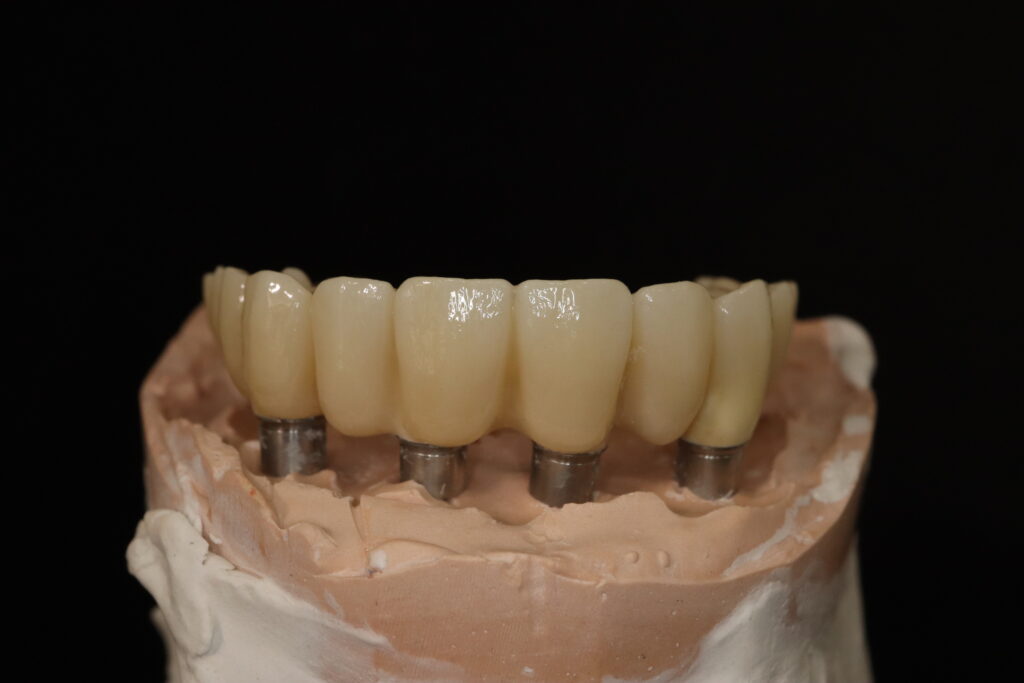

Лечение начато с выбора материала для будущей конструкции (диоксид циркония) и цвета.

Был установлен временный протез из PMMA, максимально воссоздающий форму и цвет (А3) будущей конструкции.

Спустя 20 дней был зафиксирован протез с опопрой на дентальные имплантаты из диоксида циркония.

результат имплантации